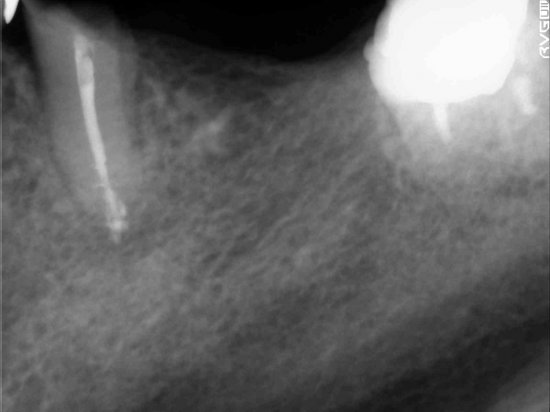

神経治療

今回は神経治療についてお話させていただきます

患者様の治療で代表的なものです

見えない根の先端をさわる治療ですので非常に難度が高いです

処置前

歯が折れて来院されました 神経が生きており痛みがありました

レントゲンで神経治療必要性をご説明させていただきました

通院が困難で治療回数を減らしてほしいとのご希望がございましたので同日神経治療を終わらす御提案をさせていただきました

処置後

ポイントは

唾液などの感染物を入れないようにすること

お薬がきっちり詰めれる形をきれいにつくること

レントゲンのように根の先までお薬を緊密に詰めること

処置後患者様にレントゲンで確認していただきご満足いただけました